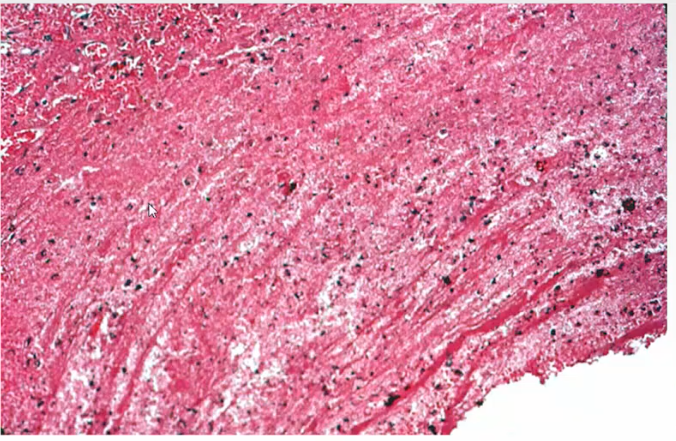

What are some of the things that are common in aorta

These are usually silent manifestation

Lines of Zanes, thrombosis, healing, thrombosis, healing